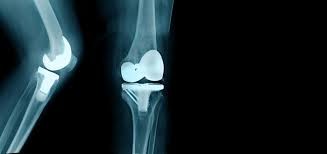

- Types of Knee Replacement Surgeries We Arrange

- Total Knee Replacement (TKR) Unilateral & Bilateral

- Robotic / Computer-Assisted Knee Replacement